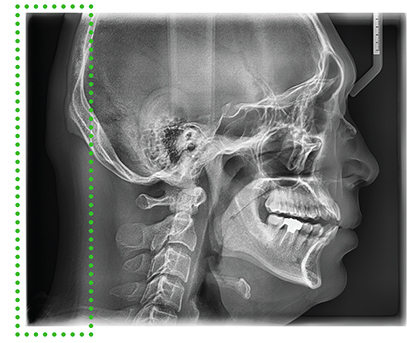

Цефалометрические изображения (Цефалостат не входит в базовую комплектацию)

Цефалометрическое сканирование предоставляет возможность получения не только стандартных латеральных, но и полных латеральных снимков черепа. Полные латеральные снимки превышают стандартные на 30%, что значительно улучшает точность и полноту ортодонтической диагностики.